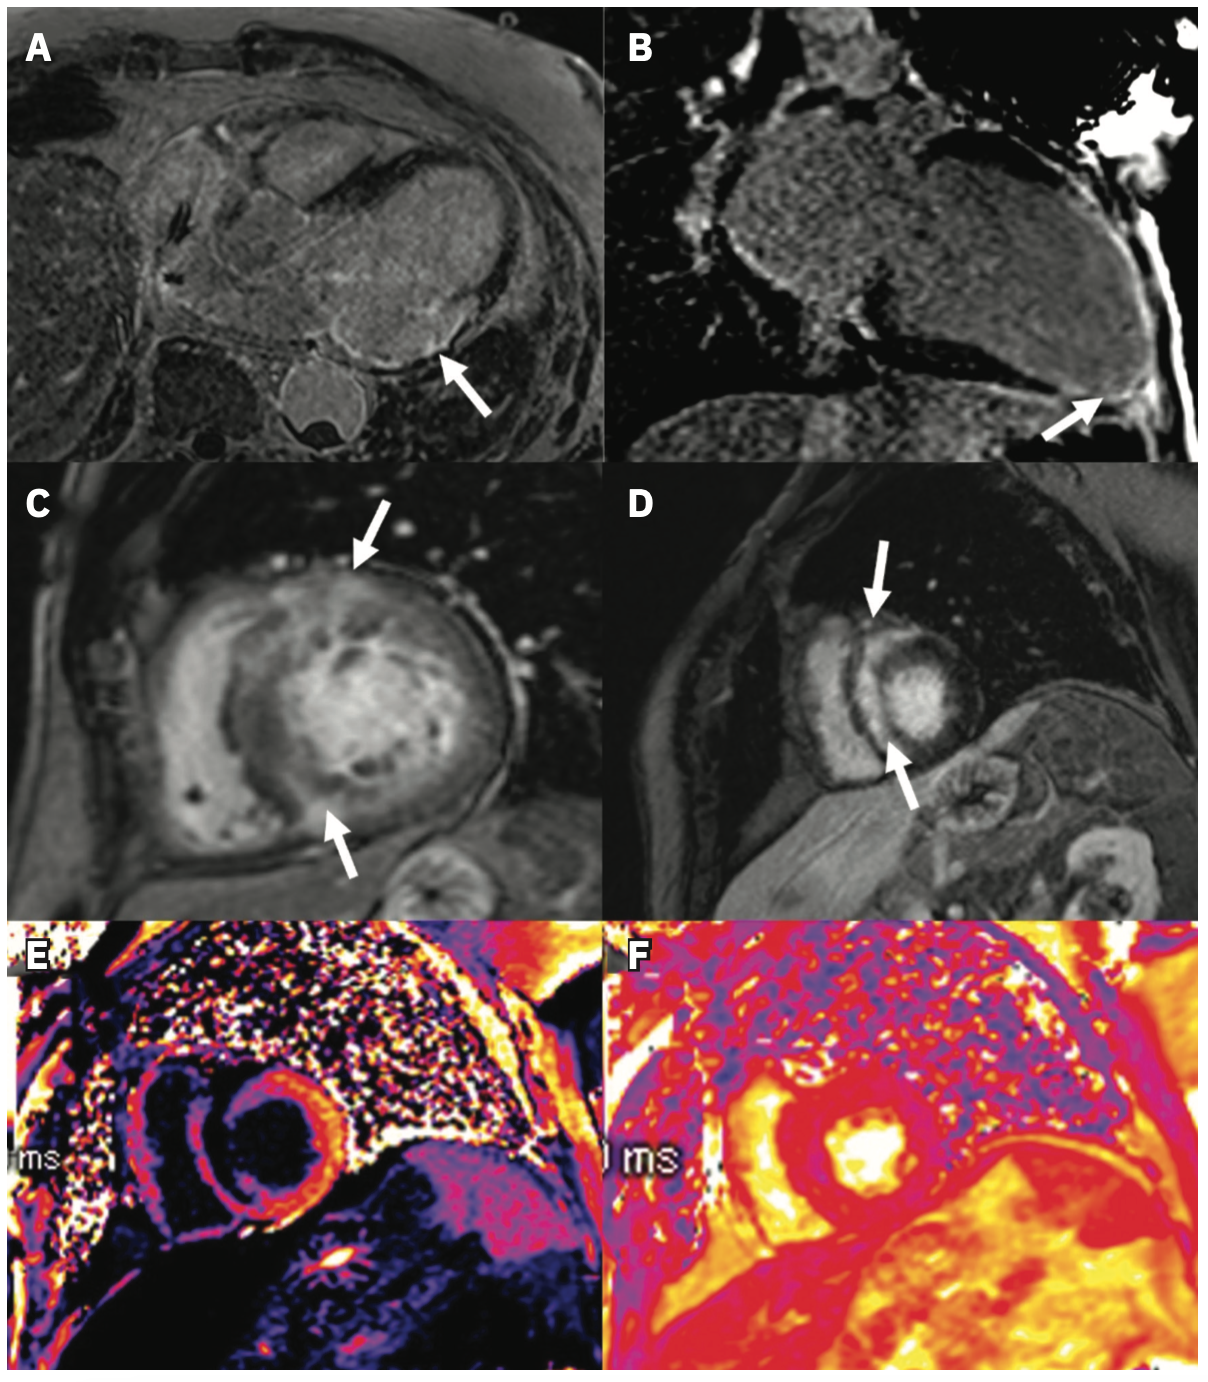

LGE assessment is well-established in clinical practice, particularly as a diagnostic tool, and its association with VA is widely described.3,4 We include examples of LGE identified in patients with ICM (Figure 1A, 1B) and NICM (Figure 1C, 1D). Several studies among patients with ICM and ICDs have shown that characteristics of LGE based on regions of heterogeneous scar termed gray zone (GZ) predict VA after controlling for comorbidities and patient level factors.5-7 Recently, it has been demonstrated that this association is not unique to low EF cohorts; among patients with an average EF of 46%, GZ mass was a better predictor of SCD than left ventricular (LV) EF.8 More complex assessments of scar and GZ have also been developed, such as LV entropy, a means of quantifying the distribution of pixel intensity of LGE.9,10 Entropy may have a stronger association with outcomes than the presence or mass of LGE and is perhaps a quantitatively richer metric.10,11 More directly regarding the outcome, LGE has also been used to identify conducting channels in CAD, mechanistically central to VA sustainability.12 Notably, this was also applicable in a mixed ICM/NICM cohort, wherein the presence of these channels and their mass was associated with VA risk.13 An example of CMR with associated electroanatomic voltage mapping data is shown in Figure 2.

Similar to how a moderately reduced or preserved EF does not fully encapsulate patients’ risk, there are also patients without LGE who nonetheless develop VA.28 Other CMR measures, including extracellular volume (ECV) (Figure 1E) and native T1 mapping, may prove useful for these and cardiomyopathy patients at large. Compared to LGE identifying localized fibrosis, ECV and native T1 are measures of diffuse fibrosis.29,30 In a study of DCM patients, of whom 73% had no LGE on CMR, native T1 was associated with all-cause mortality independent of LGE extent and EF.31 A smaller study specifically among HCM patients without LGE demonstrated a similar association of native T1 with SCD.32 Interestingly, in a mixed cohort of ICM and NICM, while native T1 was independently associated with VA, a measure based on GZ thresholds (ie, LGE) was more strongly associated with the outcome.33 For completion, we mention T2* mapping (Figure 1F), which has typically been used to identify pathologic iron accumulation in storage diseases but has recently been applied to fibrosis assessment.34-36 Further research is warranted to determine the role of T2* mapping for VA risk prediction.